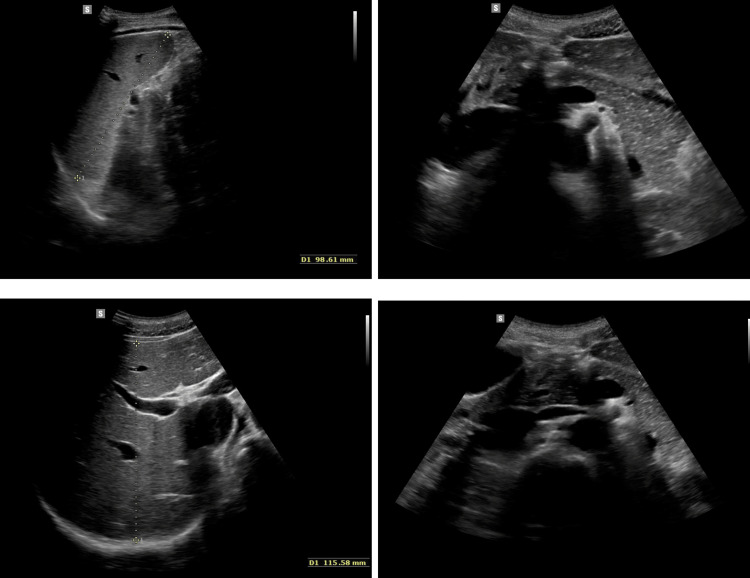

On admission, the patient’s general condition was good, weight was 56.08 kg (10-25 percentile), height was 173 cm (10-25 percentile), and BMI was 16.9 (75-90 percentile). No significant deviations were observed on physical examination. On the day of admission, laboratory tests, abdominal ultrasound (Figure 1), chest X-ray (Figure 2), lactose test, and fecal calprotectin levels were normal. However, in the afternoon, repeated vomiting was observed, initially with bile, then with large amounts of saliva, accompanied by agitation, profuse sweating, motor restlessness, and hand tremors; the patient was also aggressive toward his mother and medical staff. Attention was drawn to the boy’s inadequate behavior: fear, calling for his mother, then aggression, and declaring a desire to escape from the ward. For this reason, urine toxicology tests were ordered, in which the presence of tetrahydrocannabinol was confirmed. Upon conducting a more thorough investigation, the patient confirmed the use of the substance a few days before admission to the clinic. A conversation was held with the mother regarding the child’s use of psychoactive substances, and she declared that she knew about the problem and for this reason, attended a psychologist with the child. Each time the onset of symptoms occurred after ingestion of food xenobiotics (including alcohol and marijuana), the patient confirmed the temporal relationship between the onset of symptoms and ingestion of xenobiotics. In addition, a history of cigarette smoking is currently denied. The patient confirmed a temporal relationship between psychoactive substance use and alcohol consumption.